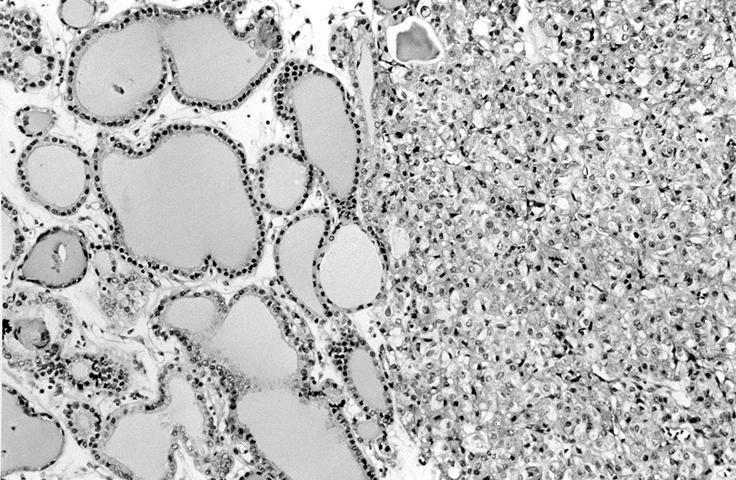

Microscopic (histologic) images

Contributed by Shipra Agarwal, M.D., Andrey Bychkov, M.D., Ph.D., Mark R. Wick, M.D., Asmaa Gaber Abdou, M.D. and AFIP

Patterns:

Microscopic (histologic) description

- Architecturally and cytologically different from surrounding gland

- Compression signs in surrounding thyroid tissue

- Encapsulated; thin or moderately thick capsule

- Architectural patterns (can be seen in any combination)

- Normofollicular (simple): size similar to normal thyroid follicles

- Microfollicular (fetal): smaller follicles, small amount of intraluminal colloid

- Macrofollicular (colloid): large follicles, flattened epithelium, abundant colloid

- Solid / trabecular (embryonal): minimal or no colloid

- Focal papillary pattern, occasionally; especially in hyperfunctioning adenoma and follicular adenoma with papillary hyperplasia

- Cuboidal to low columnar cells

- Small round nuclei, smooth nuclear boundary, uniformly hyperchromatic or euchromatic, dense chromatin, absent nuclear features of papillary thyroid carcinoma, nuclear score 0 or 1 (JAMA Oncol 2016;2:1023)

- Inconspicuous nucleoli

- Rarely, lipid filled vacuoles in cytoplasm

- Mitoses are uncommon

- Scant stroma

- Secondary changes: fibrosis, hyalinization, hemorrhage, hemosiderin deposition, edema, cystic degeneration, calcification, osseous or cartilaginous metaplasia

- Variants

- Hyperfunctioning adenoma (Plummer adenoma): tall columnar epithelium, papillary infoldings, vacuolated cytoplasm, watery colloid showing scalloping

- Follicular adenoma with papillary hyperplasia: cystically dilated follicles, intraluminal papillae

- Lipoadenoma: adipocytic metaplasia of the follicular adenoma

- Follicular adenoma with bizarre nuclei: may be seen after radiation exposure and in hyperfunctioning adenoma

- Signet ring cell follicular adenoma: signet ring cell change

- Clear cell follicular adenoma: follicular adenoma with clear cell change

- Spindle cell follicular adenoma: spindle cell metaplasia

- Black follicular adenoma (black pigment in tumor cell cytoplasm; in patients on minocycline therapy)

- No capsular or vascular invasion after thorough sampling (at least 10 blocks)